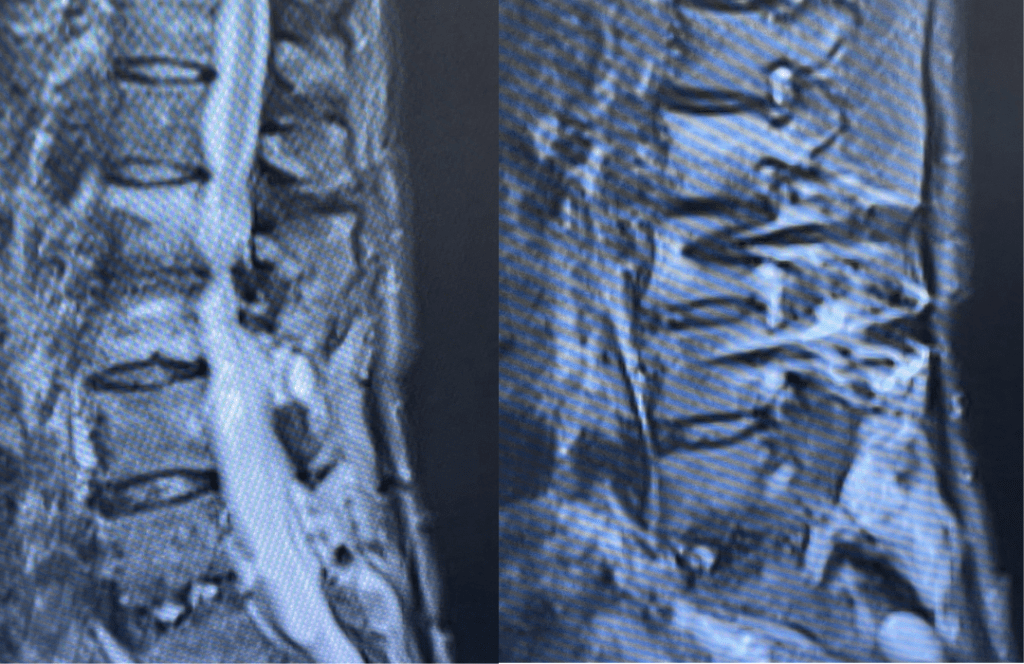

Figure 2. Axial T2 MRI of the lumbar spine demonstrating L2-3 stenosis due to significant facet arthropathy.